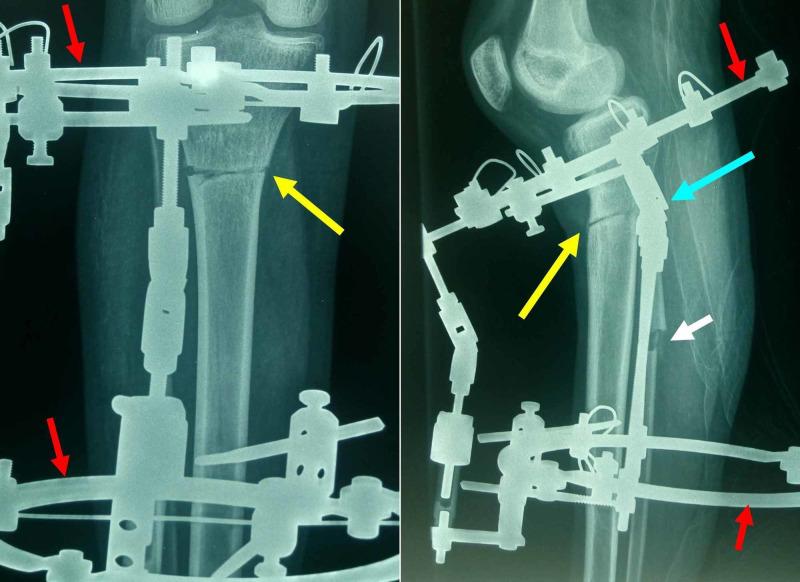

A case of unilateral genu recurvatum (GR) in a 15-year-old boy with a history of Guillain-Barre syndrome (GBS) and subsequent bilateral drop-foot is presented. Muscle imbalance of the lower limb and repetitive pressure from prolonged usage of an orthosis to deal with drop-foot may be the causative factors for early partial physeal arrest of his right proximal tibia. The result was a right GR and a shorter right lower limb. A below the tibial tuberosity anterior opening-wedge oblique proximal tibial osteotomy was performed. The deformity was gradually corrected using an Ilizarof circular frame. The center of rotation and angulation of the procedure was placed at the posterior tibial cortex. The procedure was completed uneventfully within four months. Excellent clinical and radiological improvement of the deformity was obtained.

本文报告了一例15岁男孩,有格林-巴利综合征(GBS)病史并继发双侧足下垂,出现单侧膝反屈(GR)的病例。下肢肌肉失衡以及长期使用矫正器治疗足下垂所产生的反复压力,可能是其右胫骨近端早期部分骨骺阻滞的致病因素。结果导致右膝反屈和右下肢缩短。进行了胫骨结节下方前开口楔形近端胫骨截骨术。使用伊里扎洛夫环形外固定架逐渐矫正畸形。手术的旋转和角度中心位于胫骨后皮质。手术在四个月内顺利完成。畸形在临床和影像学上均得到了显著改善。